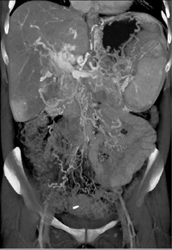

Calcifications in the Aortic Valve